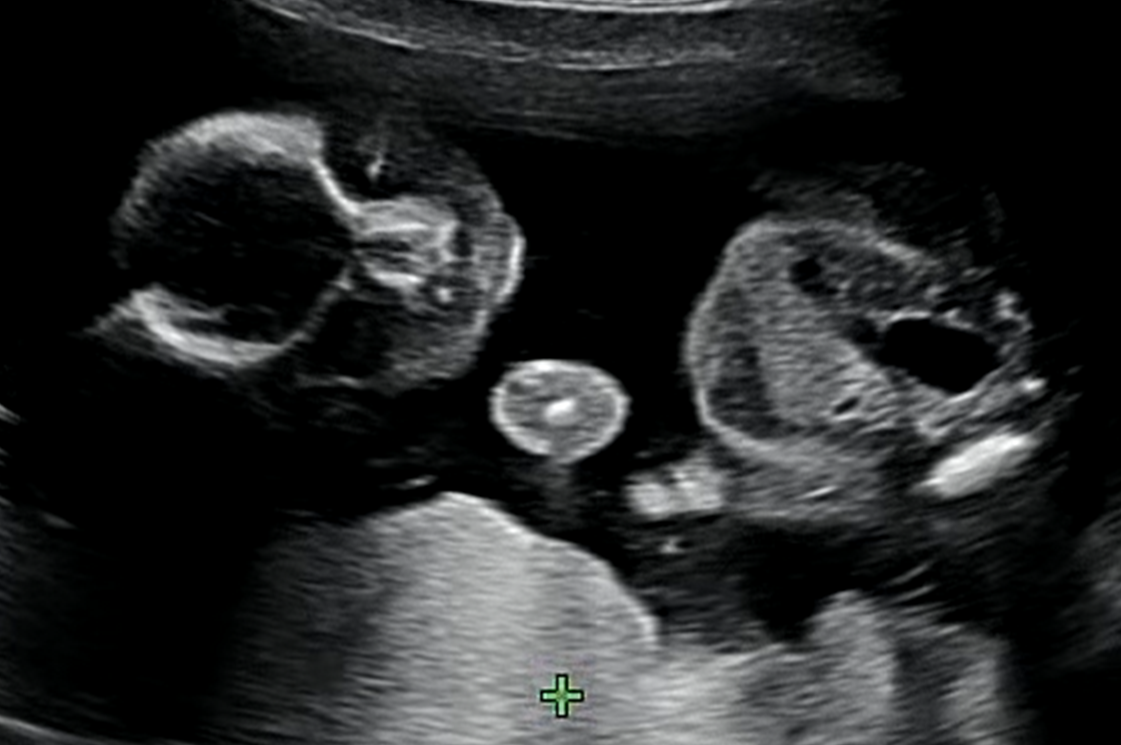

호띵이는 건강하게 잘 크고 있다. 그리고 이번 초음파에서는 호띵이 얼굴을 간접적으로 볼 수 있었다.

위의 사진을 보면 눈/코/입이 잘 크고있음을 볼 수 있다. 예정일도 8/9일 로 앞당겨졌고 앞으로 얼마나 더 잘 클지 기대된다.